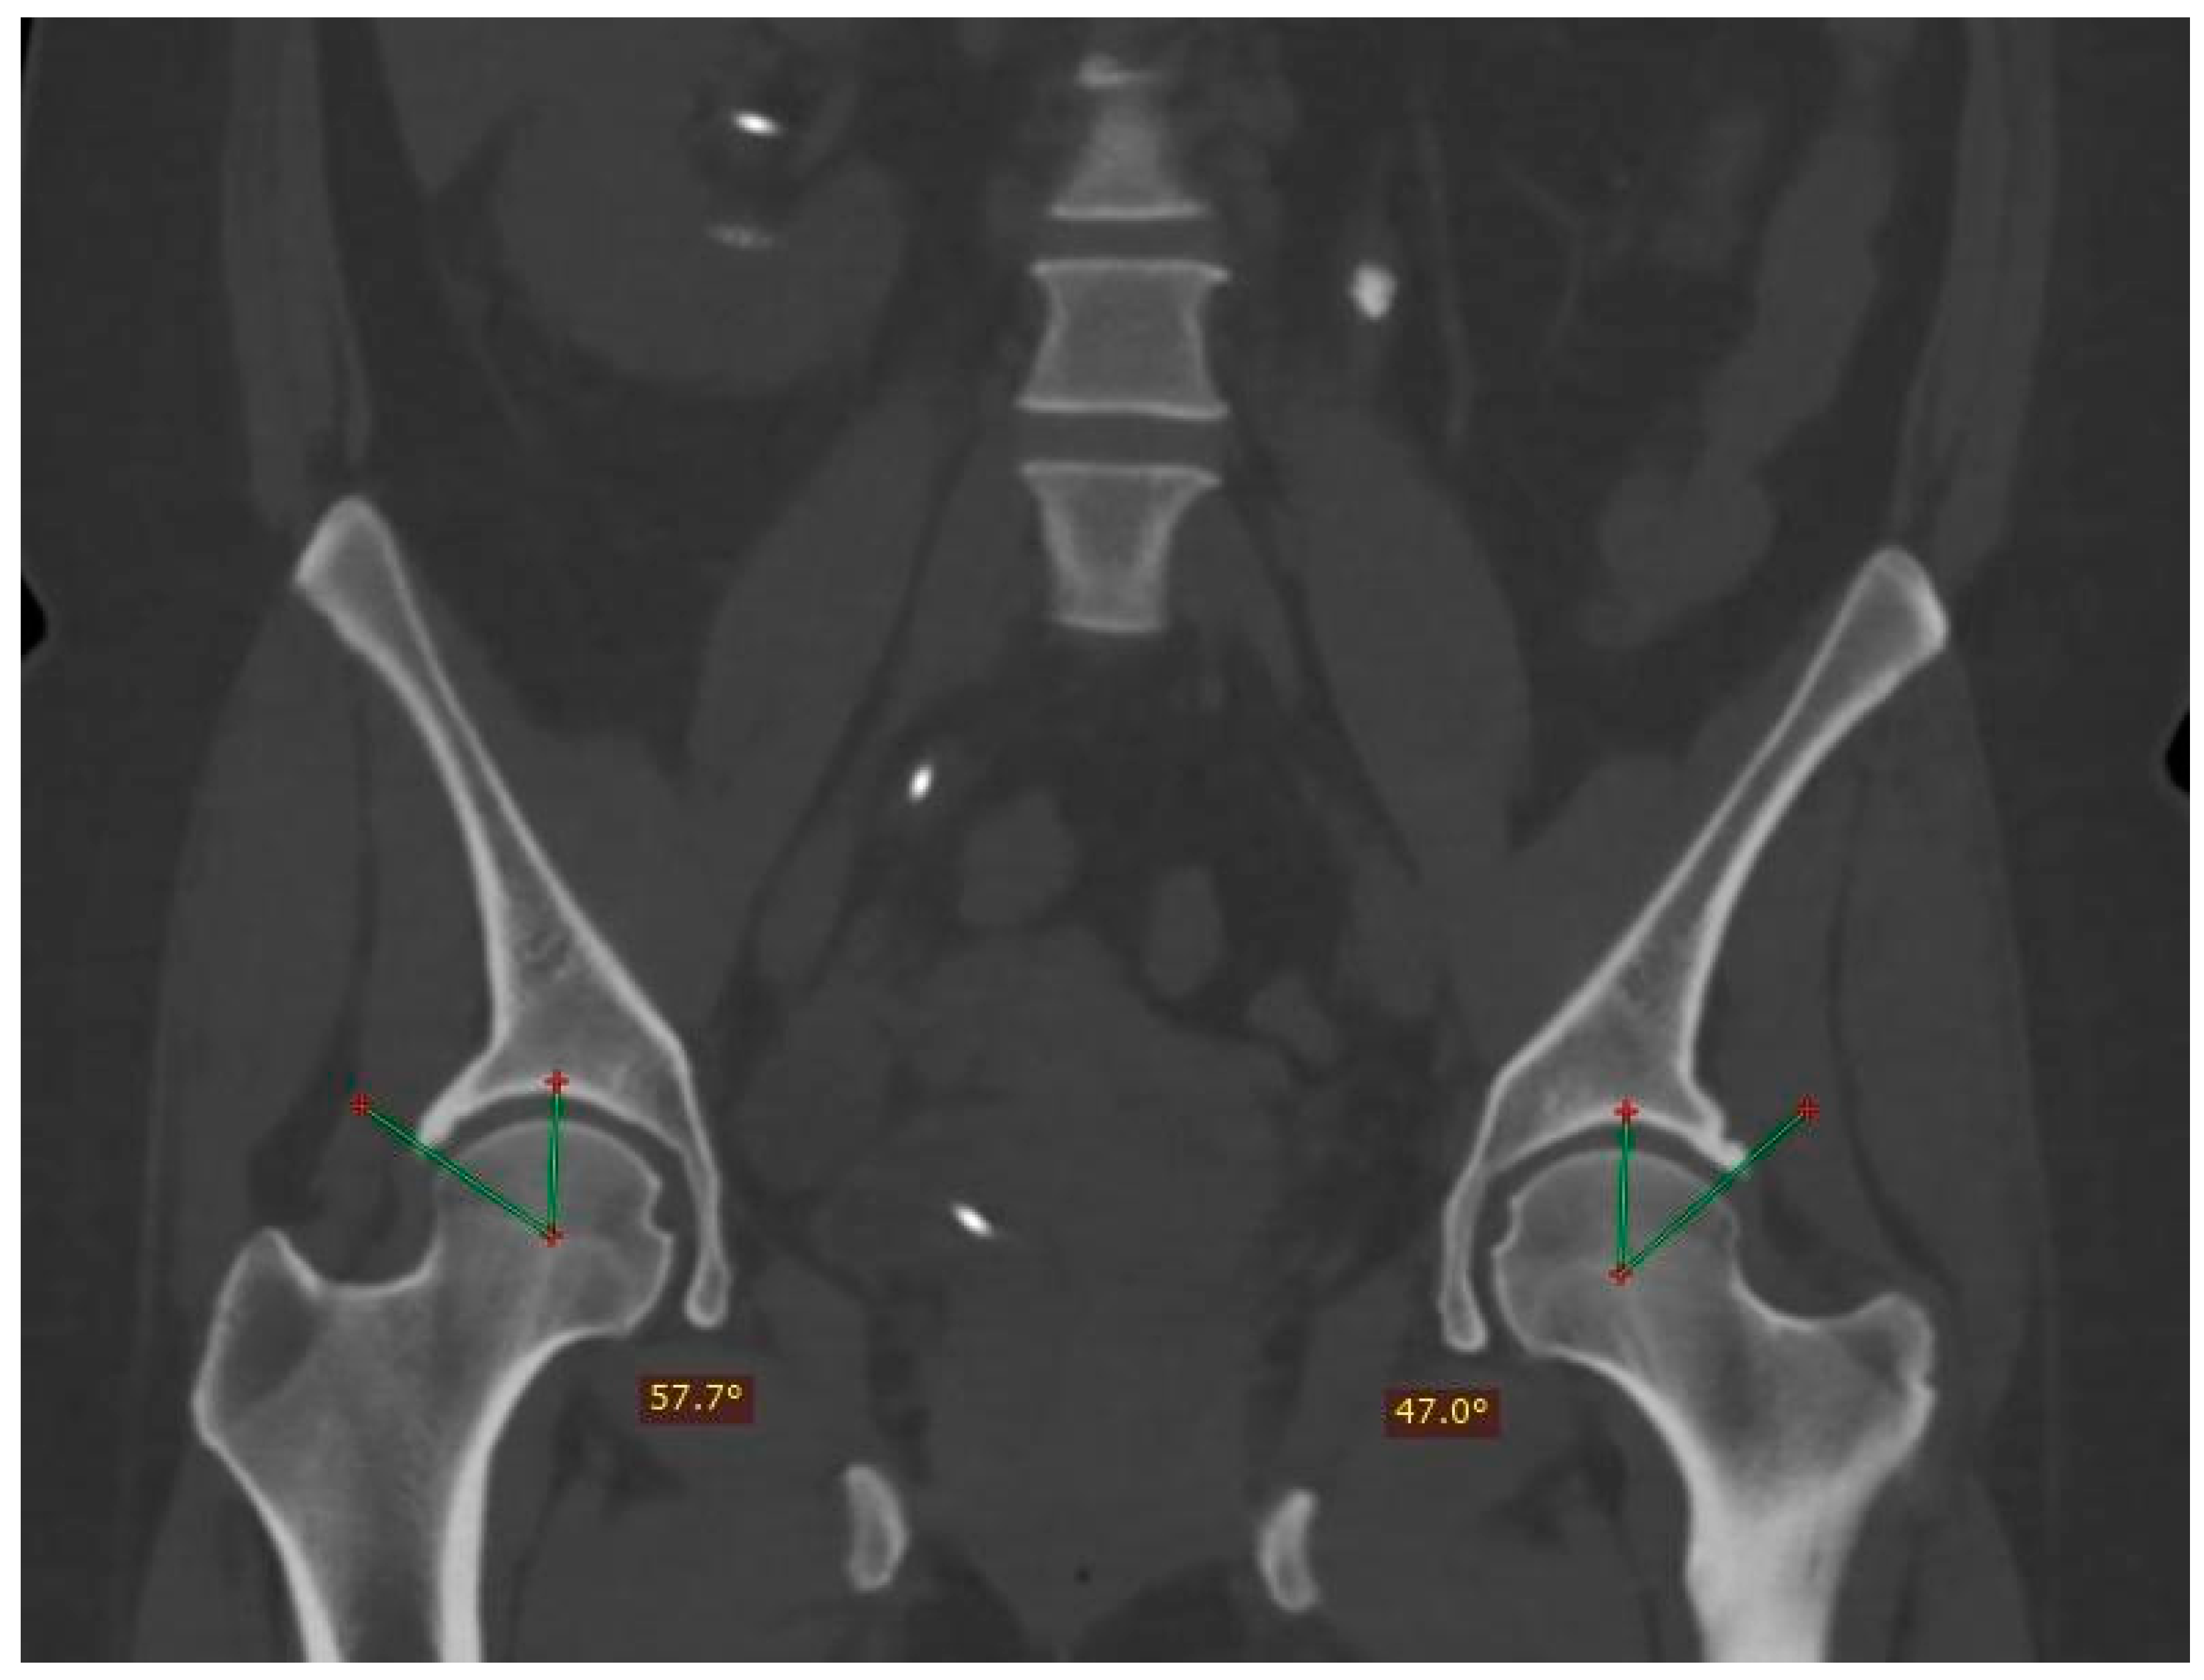

Patients who had compressive symptoms more often presented with C-sign, mixed impingement with 16.66% differences in Wiberg’s angle in patients with and without C-sign; furthermore, the average of the angles was greater in patients with C-sign, with a difference of 0.8112 degrees in the right angle and an even more pronounced difference between the averages of the left angle, at 2.7715 degrees (measurement of the Wiberg angle is depicted in Figure 3).

Figure 3.

Measurement of the center-edge angle (Wiberg) in an asymptomatic patient. An angle is obtained starting from the center of the femoral head, with a stroke following the vertical axis of the same (90°) and the lateral edge of the acetabulum. The normal value is less than 40°.